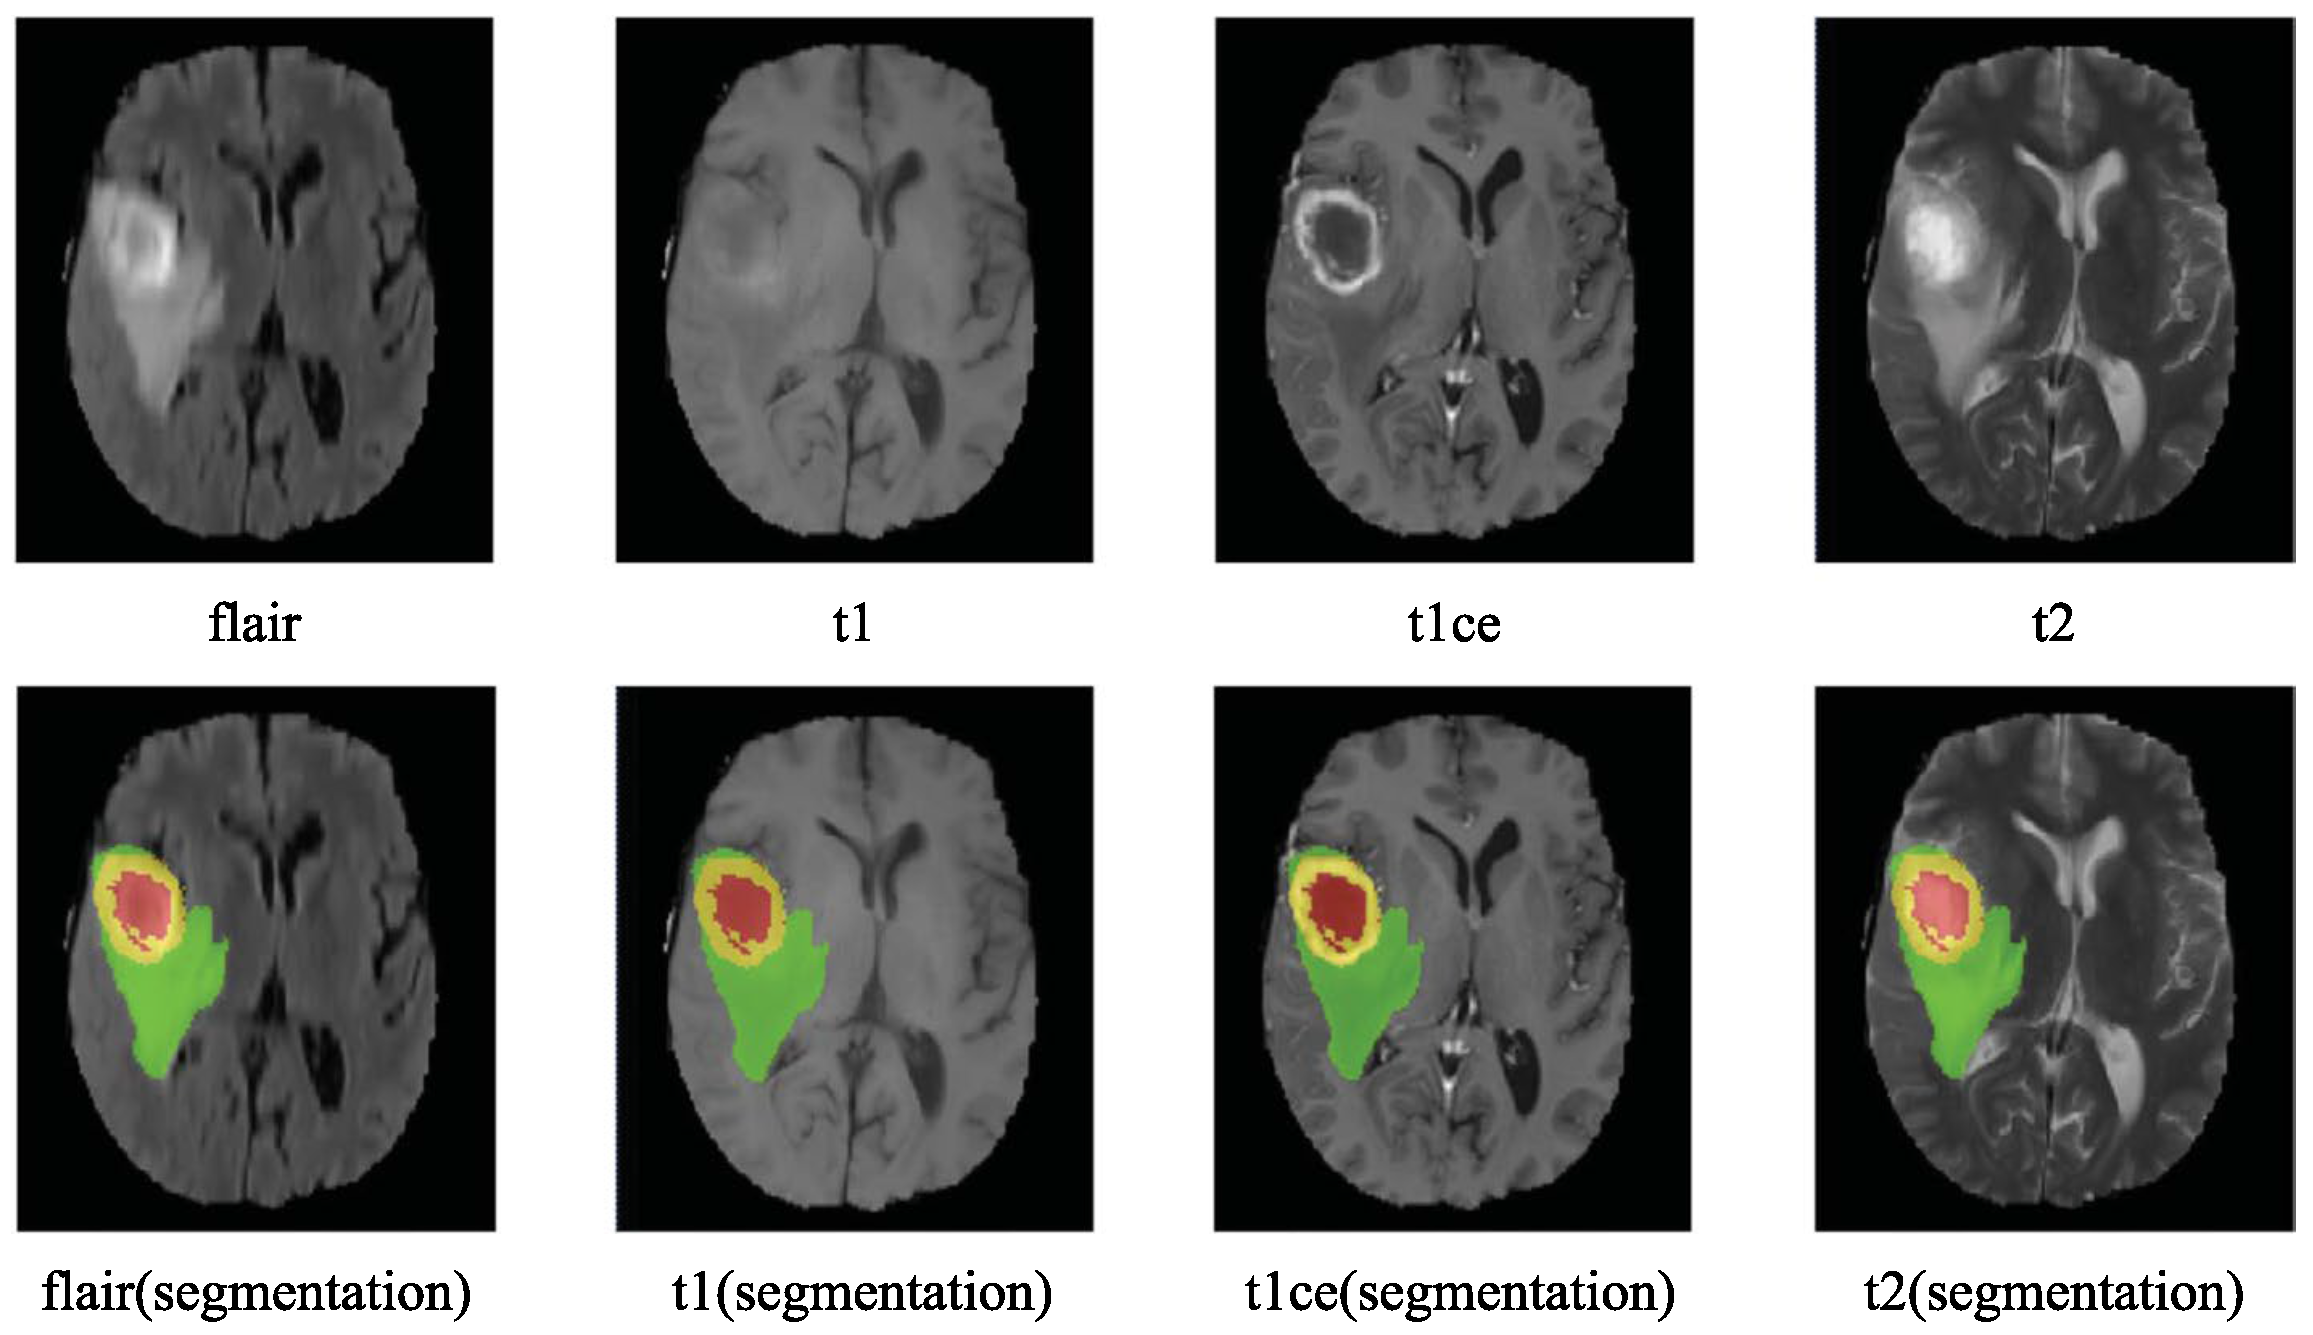

- Number of tasks: 1: Multimodal Brain Tumor Image Segmentation—segmentation of gliomas in pre-operative scans.

- Initial number of classes: two class labels:

- Label 1—ED: edema;

- Label 2—TC: tumor core.

- Final number of classes: four class labels:

- Label 1—NCR: necrotic tumor;

- Label 2—ED: peritumoral edema;

- Label 3—NET: non-enhancing tumor;

- Label 4—ET: enhancing tumor;

- Label 0: everything else.

- MRI modalities: All four modalities were available: T1-weighted, native image (T1); T1-weighted, contrast-enhanced (Gadolinium) image (T1c); T2-weighted image (T2); and T2-weighted FLAIR image (FLAIR). In subsequent BraTS challenges, these four modalities were consistently employed unless noted otherwise in the challenge description.

- Annotation Method: The simulated images were provided with predefined “ground truth” data for the location of various tumor structures, whereas the clinical images were labeled manually. They established four categories of tumor sub-regions: “edema”, “non-enhancing (solid) core”, “necrotic (or fluid-filled) core”, and “enhancing core”. The annotation protocol for identifying these visual structures in both low- and high-grade cases was as follows:

- The “edema” was primarily segmented from T2-weighted images. FLAIR sequences were used to verify the extent of the edema and to differentiate it from ventricles and other fluid-filled structures. Initial segmentation in T2 and FLAIR included the core structures, which were then reclassified in subsequent steps.

- The gross tumor core, encompassing both enhancing and non-enhancing structures, was initially segmented by assessing hyper-intensities on T1c images (for high-grade tumors) along with inhomogeneous components of the hyper-intense lesion evident in T1 and the hypo-intense areas seen in T1.

- The “enhancing core” of the tumor was subsequently segmented by thresholding T1c intensities within the resulting gross tumor core. This segmentation included the Gadolinium-enhancing tumor rim while excluding the necrotic center and blood vessels. The intensity threshold for segmentation was determined visually for each case.

- The “necrotic (or fluid-filled) core” was identified as irregular, low-intensity necrotic areas within the enhancing rim on T1c images. This label was also applied to the occasional hemorrhages observed in the BRATS dataset.

- The “non-enhancing (solid) core” was characterized as the part of the gross tumor core remaining after the exclusion of the “enhancing core” and the “necrotic (or fluid-filled) core”.